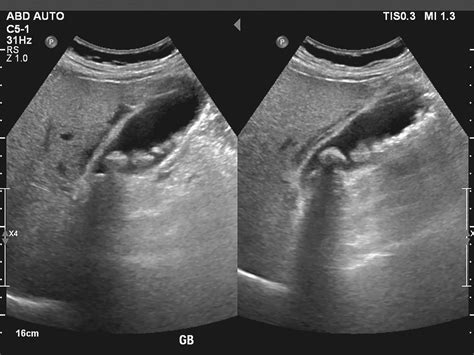

Gallbladder Stones in Singapore | Alpha Digestive & Liver Centre